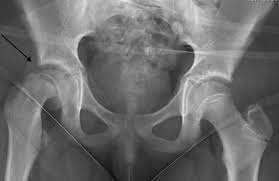

10. Kids - hip joint referral

ALWAYS sceen an adolescents hip (quick FADDIR) if they have knee pain 👃

Refers medially usually

eg Perthes (5-10), SUFE (10+)